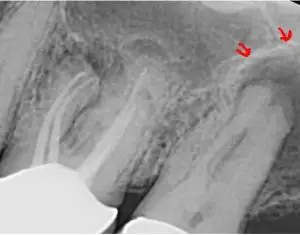

Leading the way in dental innovation, Essential Dental Systems (EDS) is proud to announce the launch of its groundbreaking product, BioSeal, a cutting-edge bioceramic endodontic